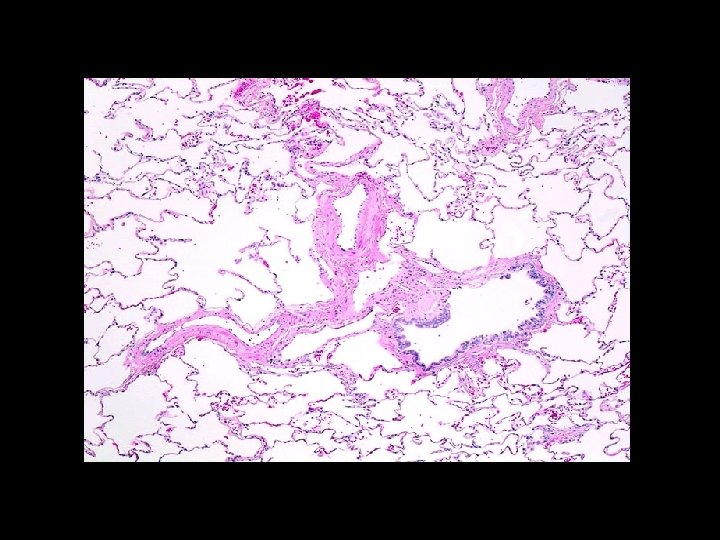

Lung Volumes § Measurement: - helium - nitrogen washout - body plethsmography § Indications: - Diagnose restrictive component - Differentiate chronic bronchitis from emphysema

Lung Volumes – Patterns § Obstructive - TLC > 120% predicted - RV > 120% predicted § Restrictive - TLC < 80% predicted - RV < 80% predicted